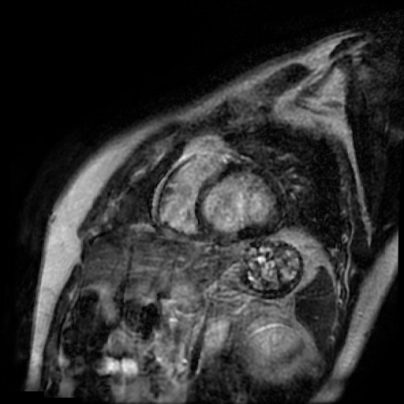

Проводилась фармакологическая разгрузка ЛЖ добутамином и левосименданом, на фоне чего отметилась положительная динамика в виде увеличения VTI до 10 см на 3 день и до 15 см на 5 день. На 6 день при минимальной вазопрессорной и инотропной поддержке и минимальной скорости потока ЭКМО, по данным контрольной ЭхоКГ ФВ ЛЖ составила 39%, VTI в выносящем тракте ЛЖ — 20 см, на фоне чего процедура ВА-ЭКМО была прекращена. Дальнейший восстановительный период осложнился развитием тромбоза в полости ЛЖ, обеих предсердий, кардиоэмболического инфаркта головного мозга, верифицированного по данным мультиспиральной компьютерной томографии головного мозга. Выполнена магнитно-резонансная томография (МРТ) сердца — картина расширения левых отделов сердца, диффузный гипокинез всех стенок ЛЖ, на фоне большого количества артефактов (частая желудочковая экстрасистолия, эпизоды ФП), достоверных признаков отека миокарда не определялось, однако в отсроченную фазу выявлено диффузное интрамуральное повышение сигнала (рис. 3). При дальнейшем наблюдении, на фоне инициации квадритерапии, проведения курса физической реабилитации отмечалась положительная динамика в виде улучшения эхо-картины (ФВ ЛЖ — 45%), полного регресса неврологических, дыхательных нарушений. Пациент был переведен в кардиологическое отделение, а на 24 сут. от начала госпитализации — выписан.

Рис. 3. МРТ сердца.